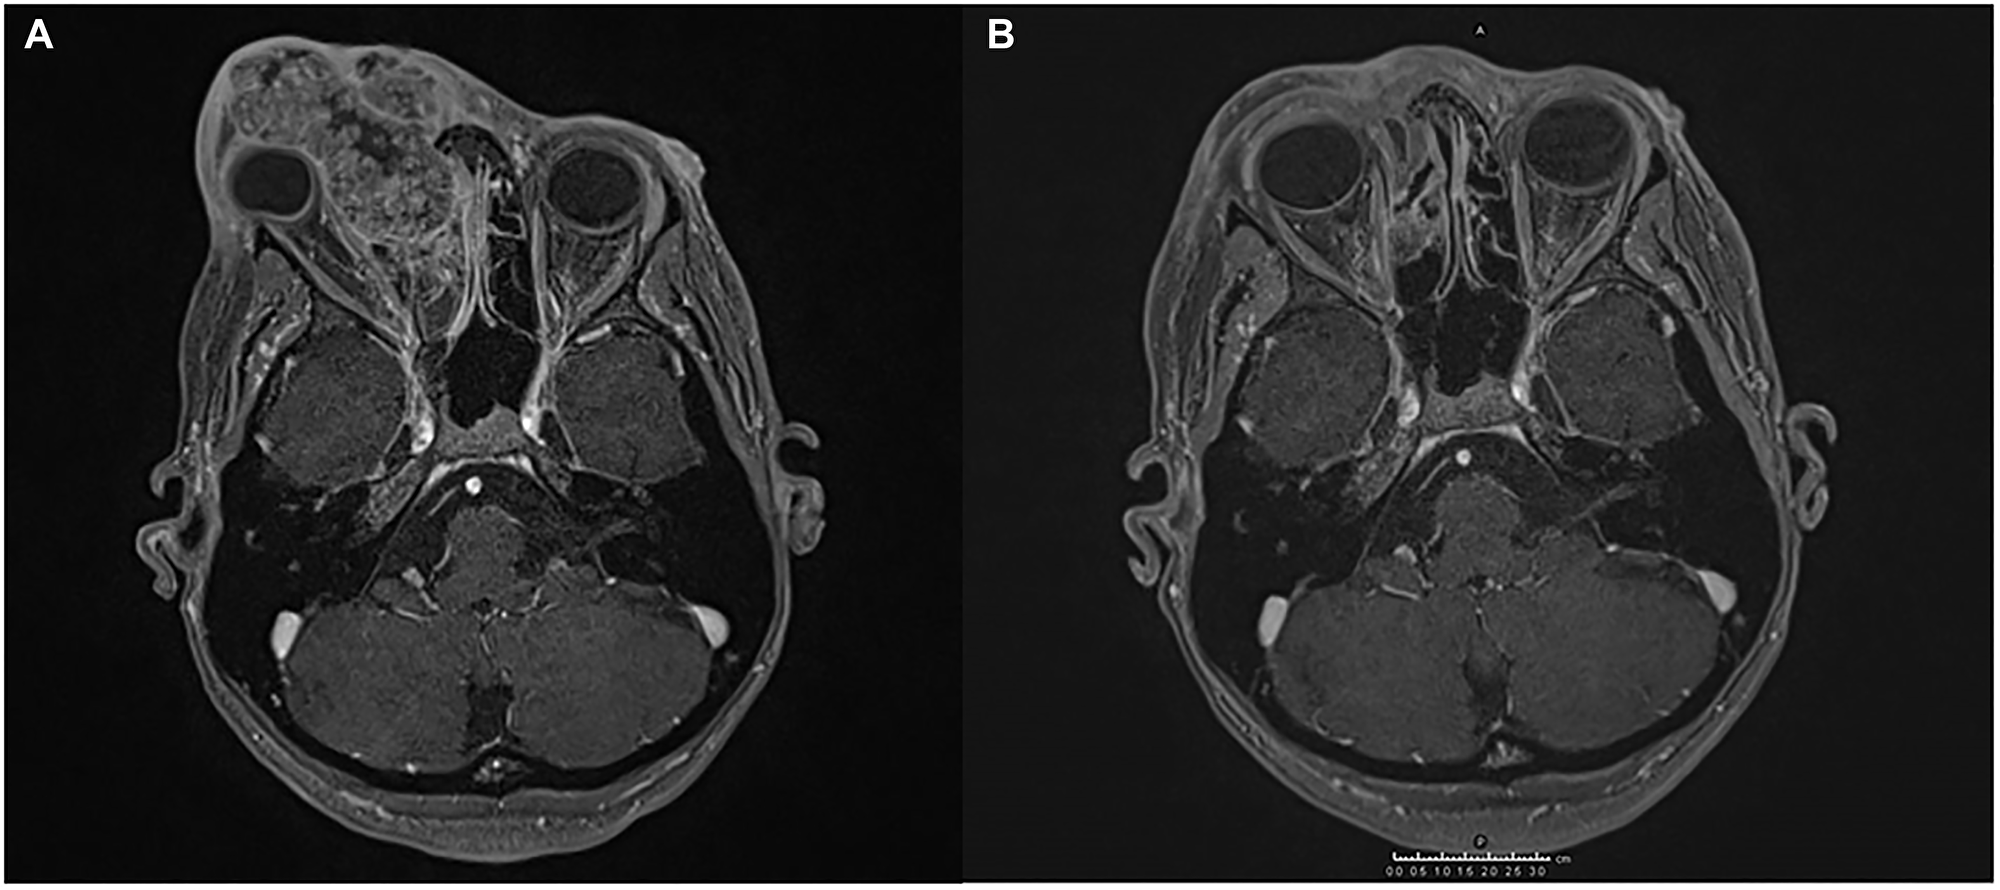

We firstly visited the patient in December 2018. On skin examination, a large hard swelling of the right superior eyelid extending to the nasal pyramid has been observed. An incisional biopsy was performed, resulting in a moderately-differentiated SCC. A CT scan was carried out to exclude secondary localizations. The MRI of the facial massif showed an infiltrating lesion of 62 × 47 mm. It extended from the right upper eyelid region affecting the orbital cavity’s medial wall and dislocating the eyeball from which it appeared inseparable. It jutted medially into the nasal cavities infiltrating the nasal septum and, below that, it crossed the floor of the orbit projecting into the ipsilateral maxillary sinus.

The interdisciplinary consultation did not indicate surgical treatment, therefore the anti PD-1 cemiplimab was requested in the nominate use programme and it was decided to add radiotherapy. Pending authorization of the drug, the patient was qualified for proton beam radiotherapy (PBR), which was performed with a total dose of 59.4 Gy in 33 fractions from January to March 2019. The treatment was well tolerated and, in consideration of the remarkable clinical and radiological response, a close clinical and radiological follow-up was established. Subsequent MRI showed stable disease with only a few spots of enhancement in the radio-treated area. (Figure 1).

Figure 1: Magnetic resonance imaging (MRI) showing the response of SCC to the treatment administered. (A) An infiltrating lesion engages the medial wall of the right orbital cavity dislocating the eyeball, and invades the right nasal cavity and the nasal septum. (B) The lesion is significantly reduced after hadrontherapy.